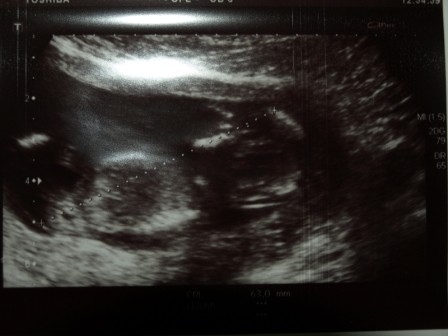

-trzecie od lewej-serduszko